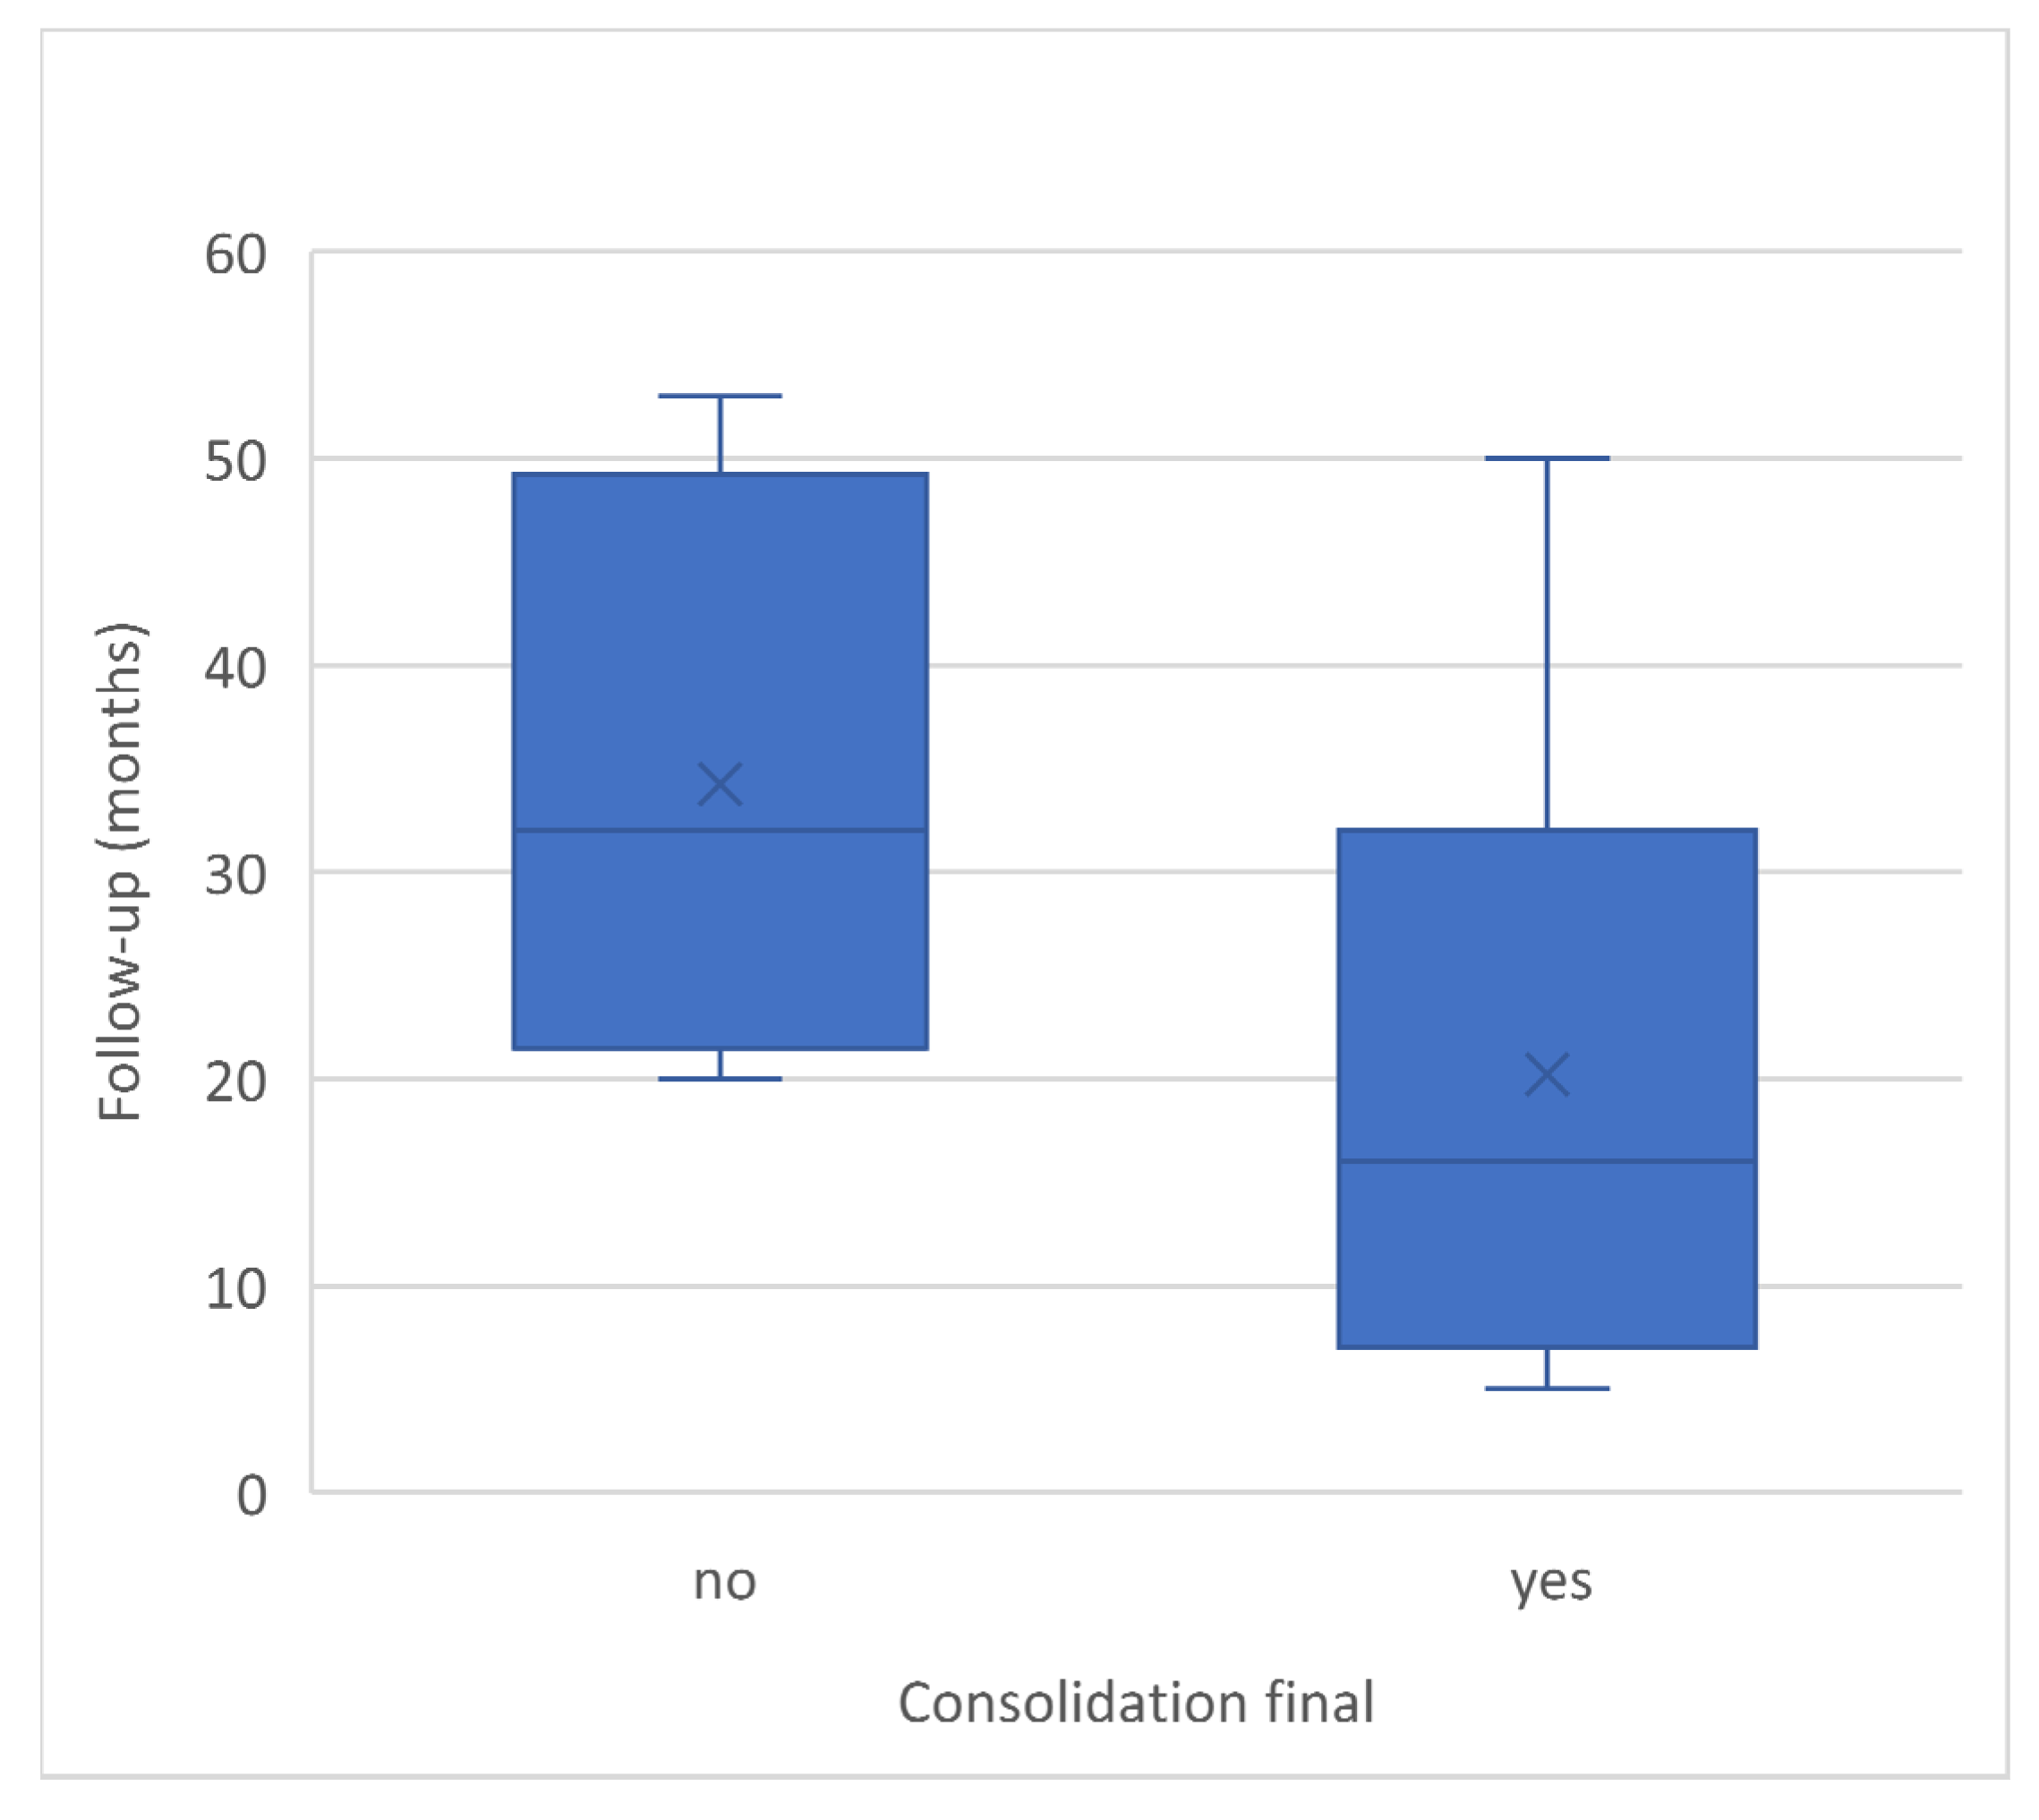

| follow-up (months) | 34.25 | 32.00 | 14.57 | 20.11 | 16.00 | 15.69 |